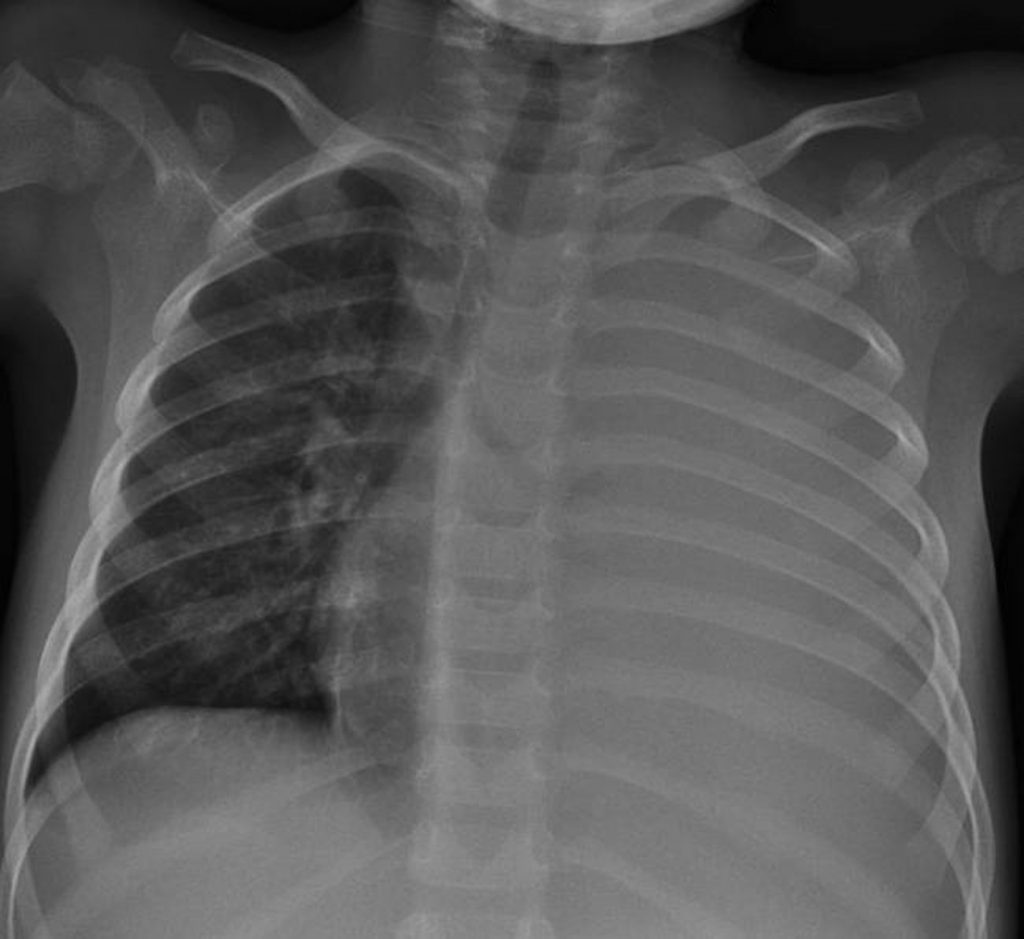

Fig. 126.2 Radiographie thoracique de face : pleuropneumopathie gauche.

Hémithorax gauche opaque refoulant la trachée et le médiastin à droite, avec visualisation de la bronche souche gauche et des bronches lobaires.

Source : CERF, CNEBMN, 2022.